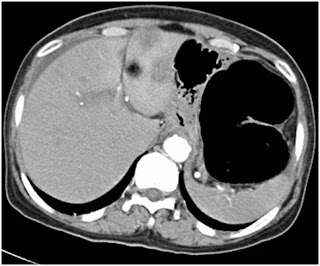

An elderly woman in her 8th decade presented with 6 months history of weight loss and progressive constipation that for last 4 days had progressed to obstipation. There was no major comorbid illness and prior to obstipation she was managing her daily activities. Her abdominal CT scan revealed obstructing lesion in rectosigmoid region with closed loop obstruction. There were multiple colorectal liver metastases in segment 2 & 3 (Figure 2 & 3).

Figure 2. Abdominal CT scan with distended left colon and CLM

At surgery, the whole of whole of large bowel was massively distended but the cecum was viable. Anterior resection with ascending colostomy was done. She opted for colostomy closure 8 weeks later but declined further chemotherapy. Following this second surgery she was restored to good quality of life and passed away 16 months later.